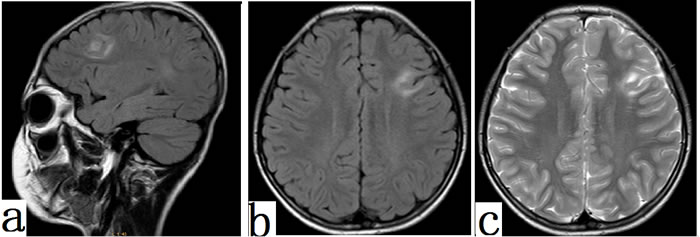

Fifty-four/sixty-seven patients had abnormal MRI results (cortical thickening, gray-white matter blurring, T2 Hyperintensity on lesions, Flair Hyperintensity on lesions). Cortical thickening and blurry gray/white matter junction were most frequently found in 40/41 (97.56%) FCD II patients. Thirty-nine/41 (95.12%) cases with FCD II had low signals on T1 but high signals on T2 (Figure 5a) and FLAIR (Figure 5b). For FCD I patients, MRI in 14/26 (53.84%) cases merely showed meager mixed hyper-intensity on T2 and mixed hyper-intensity on FLAIR signals.

Figure 5: MRI features in FCD II patients. Typical MRI features of focal cortical dysplasia type IIb. Diffuse thickening of the cortex in the left frontal lobe and areas of markedly increased signal could be seen on FLAIR (a, sagital ;b, axial) and T2 (c,axial) (arrowhead).

The MRI finding of FCD II includes increased cortical thickness, blurring of the gray-white matter junction, T2 and Flair hyperintensity on lesions [15-18]. The most sensitive MRI parameters for FCD II were cortical thickening and blurry gray/white matter junction (97.56%) and the relatively lower changes include high signals on T2 and Flair images in this study (95.12%). MRI features of FCDII may provide enough information about the location of lesion and regular EEG criteria was used for further localization, which could enable complete resection. In contrast to FCD II, MRI diagnostics of FCD I is more challenging. Colombo et al [19] and Tassi et al [20] reported MRI changes in FCD I including milder forms of abnormal signals. Of our 26 FCDI patients, 14(53.84%) had very meager signal changes and mixed hyper-intensity on Flair and T2 signals, and 12 had normal MRI. Most FCD I cases need further intracranial recording in pre-surgical evaluation.